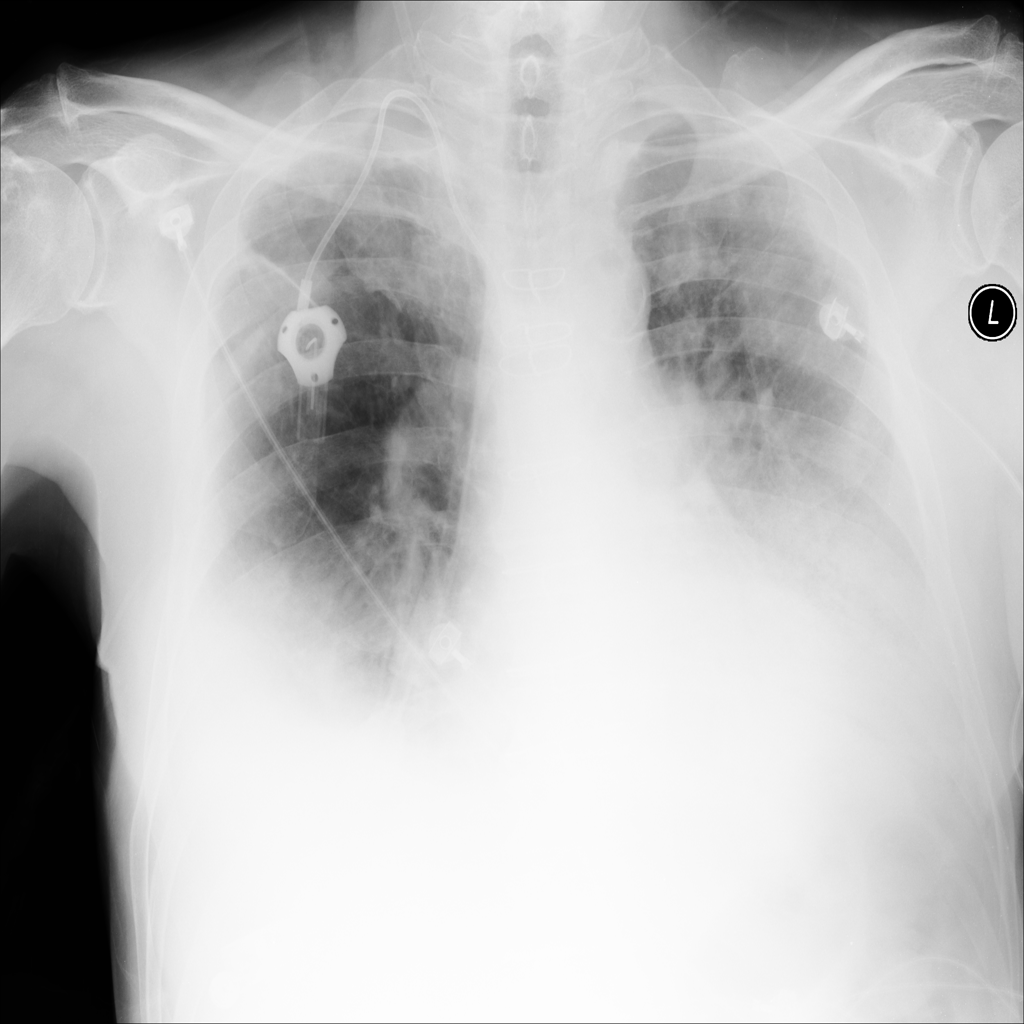

PAT-40F9 · IMG-004Effusion

PAT-40F9 · IMG-004

PA